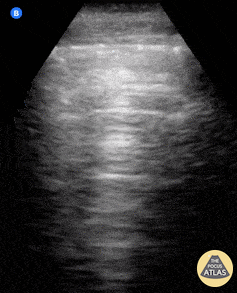

Based on the ultrasound image, which shock etiology is most likely?

1 pts